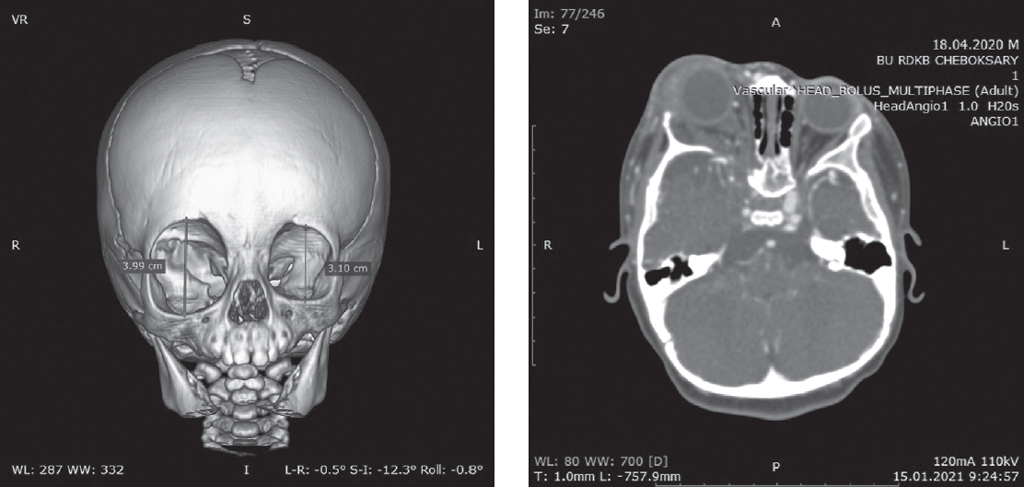

На компьютерных томограммах отмечена выраженная деформация правой орбиты: увеличение в размерах, смещение латерально и вниз, расширение верхней глазничной щели. При внутривенном контрастировании отмечается умеренное накопление контраста в мягких тканях верхнего века правой орбиты (рис. 1).

Рис. 1. Компьютерная томограмма ребенка с объемной реконструкцией и контрастным усилением: описание в тексте

Fig. 1. Computed tomography of the child with volumetric reconstruction and contrast enhancement: description in the text